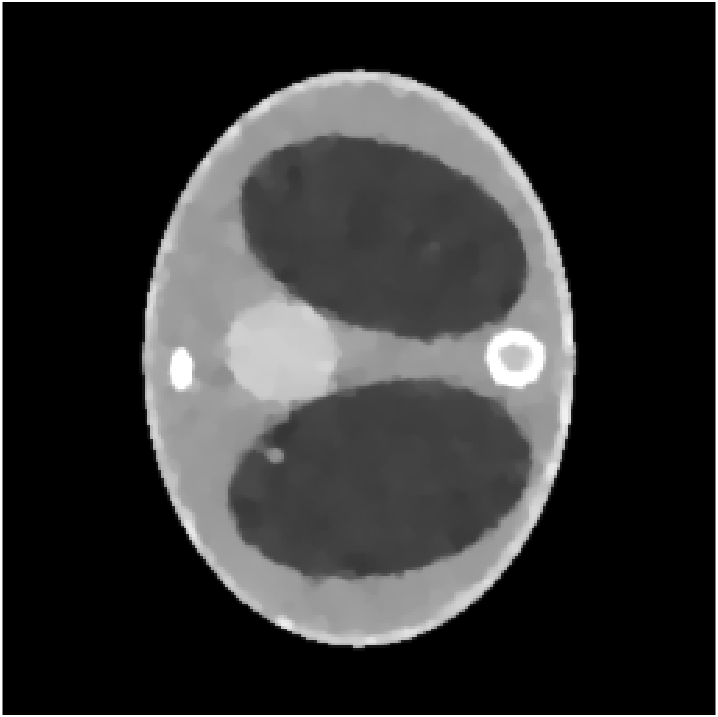

We assume to measure a total of photons and compute synthetic data from eq. 11 for a phantom electron density modeling a transversal slice of a human thorax. The phantom (see fig. 2(b)) consists of characteristic functions of ellipses of different sizes and opacities and is a modified version of an earlier phantom which was used in [12]. It is 28.4 cm resp. 21.3 cm wide at its largest and smallest diameters and its gray values are chosen as electron densities of materials typical in a human thorax [15, 3, 30].

In the reconstruction, a suitable choice for the regularization parameter is computed by the L-curve method. In fig. 3(e) we see that a reconstruction of the electron density from works well and the TV penalty term reduces the effects from the Poisson noise sufficiently. However, adding the component (fig. 3(f)) to the spectrum distorts the reconstruction. Due to the enormous noise level brought into the model by the component , the TV-regularized solution suffers from bad quality. Details are less visible or harder to localize and intensities of the different regions are altered complicating material recognition.

The method is tested for two synthetic phantoms; firstly, the thorax phantom already used in section 2. Figure 8 shows how the algorithm succeeds in decreasing the impact of the higher-order scattering. The ground truth is displayed in fig. 8(a). Expectably, the CT reconstruction (fig. 8(d)) is not accurate enough, but can be used as a prior to estimate the nonlinear weight function . Using , the CST reconstruction is computed. For comparison, we give both the solution of eq. 25 (without ) and eq. 26 (with ). As in section 2, eq. 25 cannot yield a useful reconstruction. The minimizer when is the Kullback-Leibler divergence (13) and is very noisy (fig. 8(b)) and using TV regularization, some noise can be filtered out, but only at the cost of losing small details of lower contrast (fig. 8(e)). As desired, applying to the data reduces the noise level, see fig. 8(c) and fig. 8(f) (with TV regularization). After applying , we use the norm as data fidelity measure. Densities and contrasts are accurately recovered and previously vanished details can be correctly located.